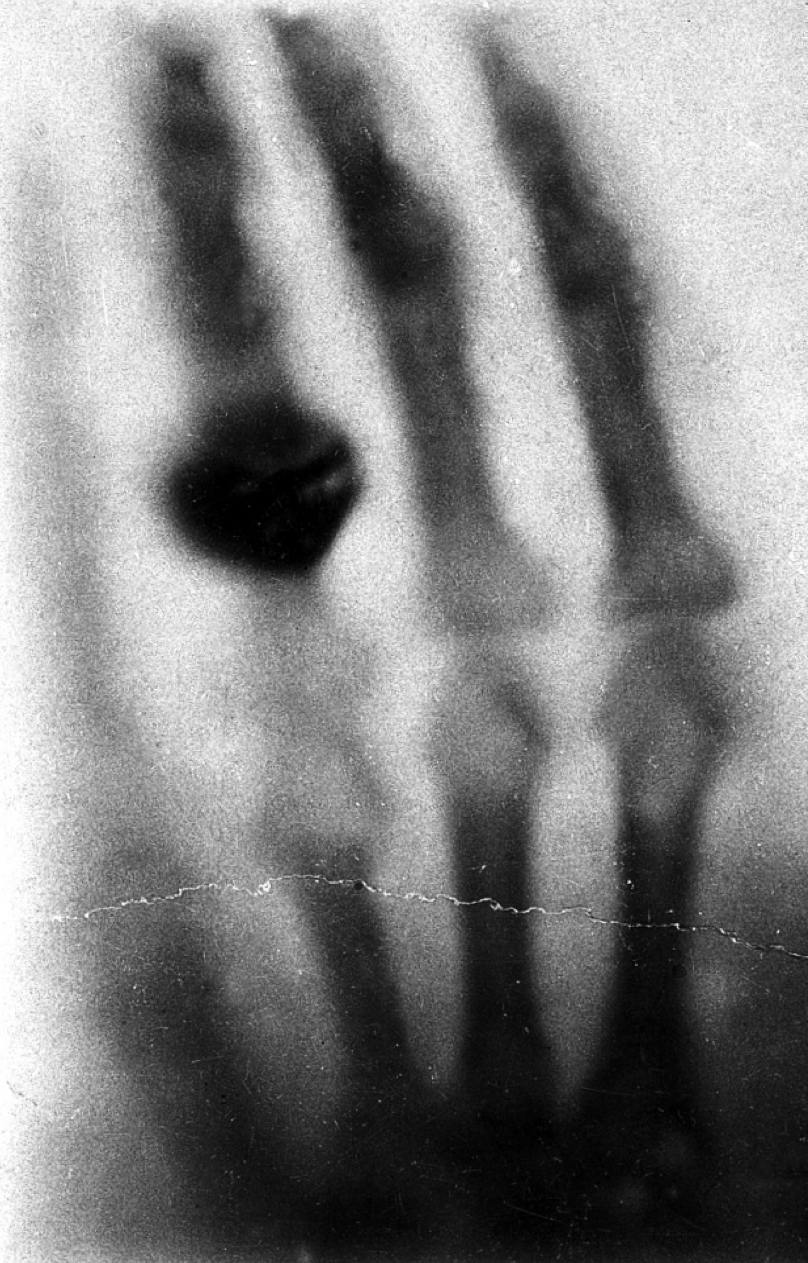

De eerste röntgenfoto, genomen op 22 november 1895.

Het is vrijdag 8 november 1895, laat in de middag, als Wilhelm Conrad Röntgen plotseling het stralingsgevoelige scherm in zijn verduisterde laboratorium ziet oplichten. Dat weekend gaat hij niet naar huis, noch de erop volgende weken: onafgebroken experimenteert hij met dit fenomeen van zogenaamde fluorescentie. Hij eet, slaapt, leeft in zijn laboratorium. Op enig moment stapt hij zelf in de stralenbundel en ziet zijn eigen skelet op het scherm verschijnen: een moment dat even opzienbarend als vreeswekkend moet zijn geweest. Twee weken later, op 22 november 1895, neemt hij dan de eerste officiële röntgenfoto, van de hand van zijn vrouw. Het eerste beeld in de radiologie is geboren.